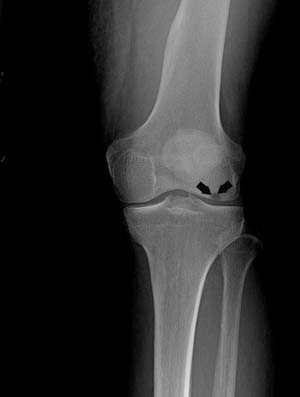

- Knee Fracture

A fracture is a condition in which there is a break in the continuity of the bone. In younger individuals, these fractures are caused by high energy injuries, as from a motor vehicle accident.